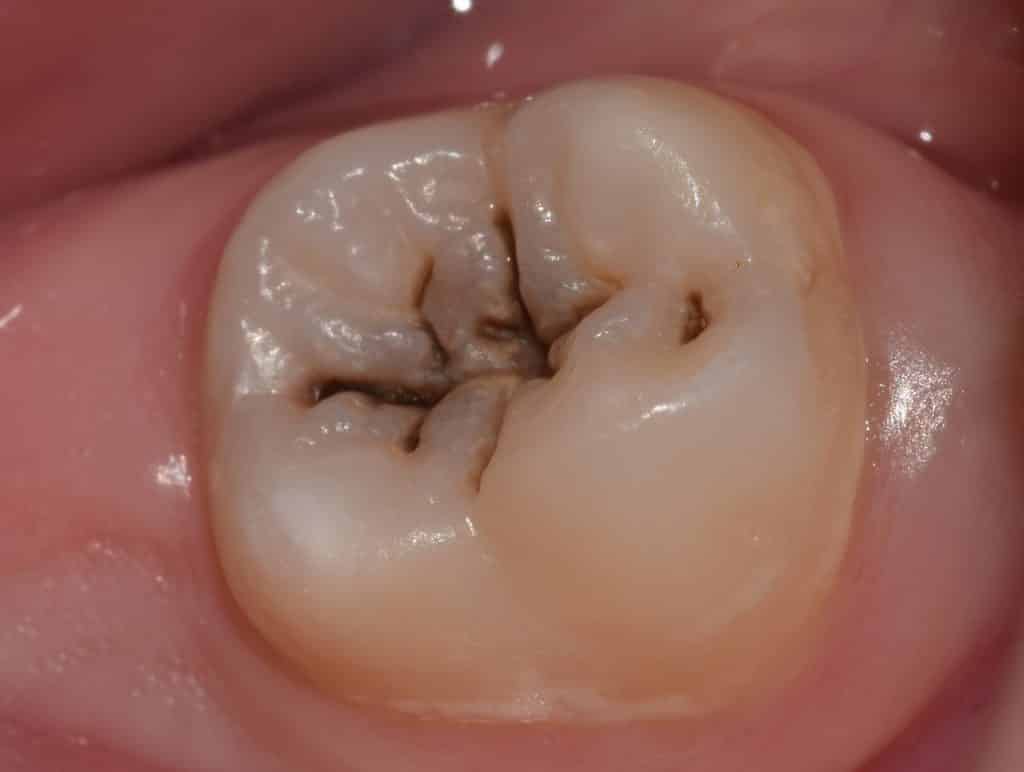

Patient came to the clinic seeking treatment for this tooth with pit and fissure caries (class 1), after examination the diagnosis was tooth with irreversible pulpitis that need a direct composite restoration as a treatment choice.

Checking of the occlusion before drilling.